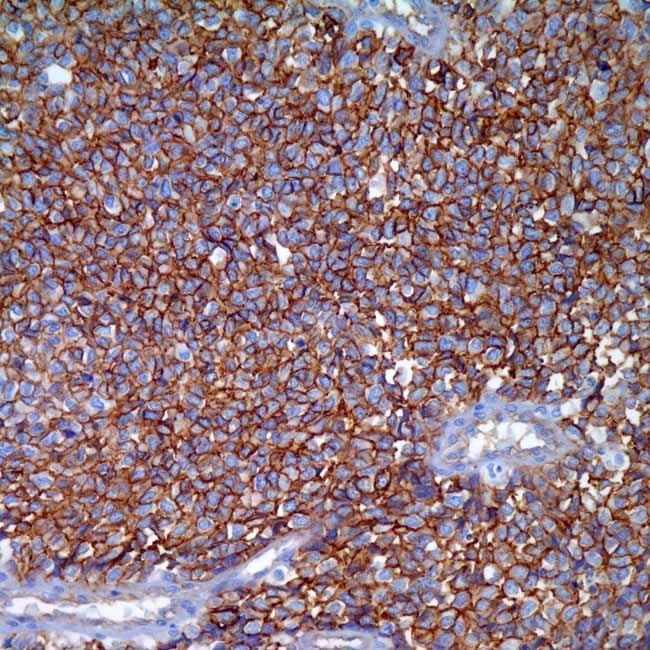

CD99 (EPR3097Y)

Visualisationmembranous

ControlEwings sarcoma, pancreas